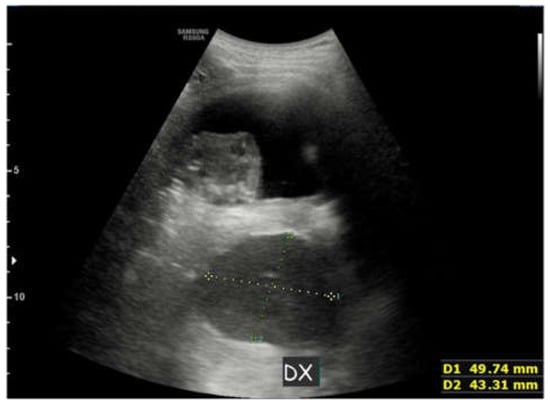

2. Case Report